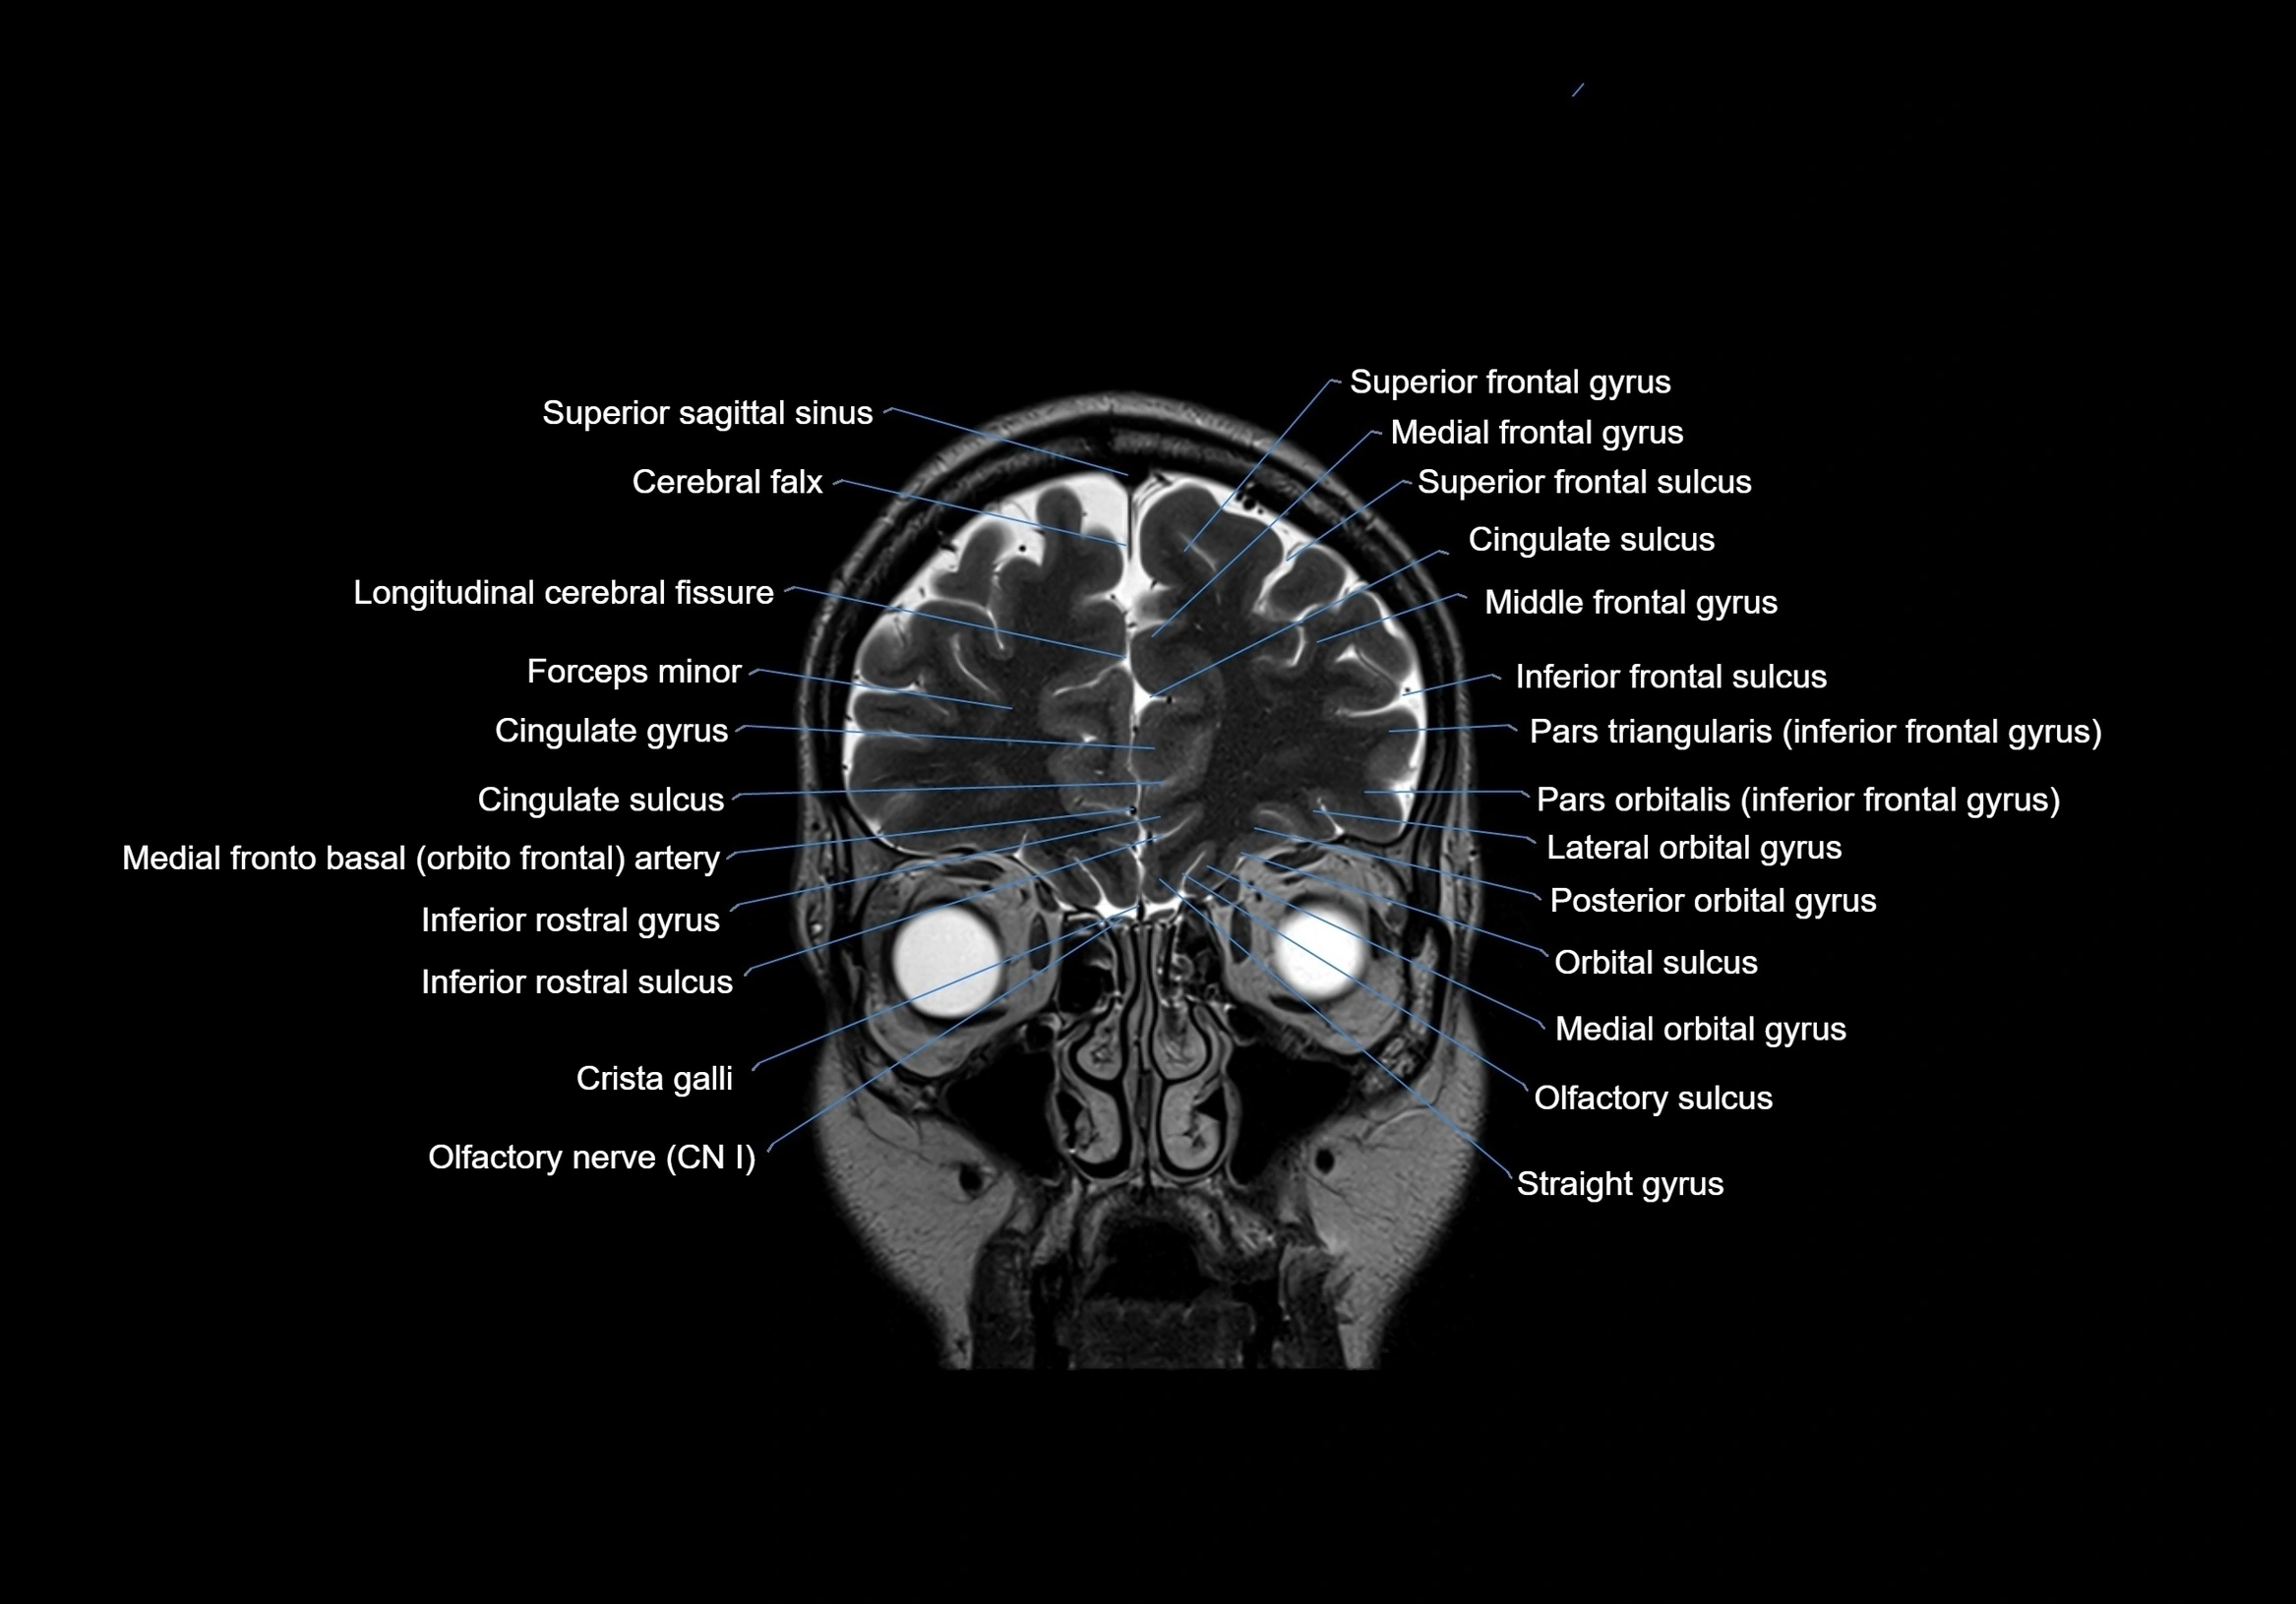

MRI images